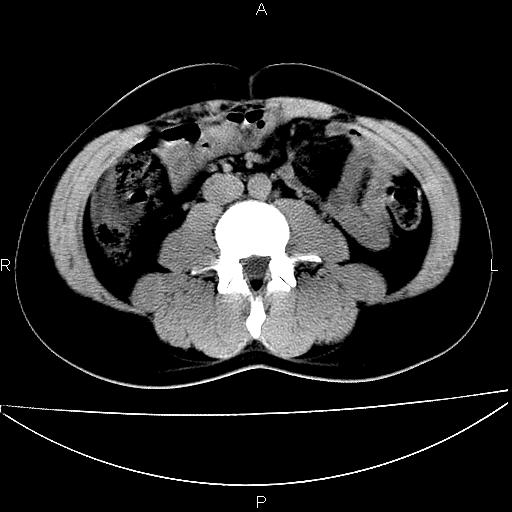

男 25岁 自述 尿频尿急,排尿困难20多天.无腰痛, b超说左肾盂轻度积水,左输尿管上端扩张.未见结石影. ct我看双侧肾盂轻度积水,双输尿管上端都扩张,大家看看能看见结石吗?

双肾轻度积水,双侧输尿管上段扩张(原因待查)。

双输尿管扩张下端未见高密度结石和输尿管晕轮征,不好说是结石.增强后如何?

考虑肾外肾盂 前列腺轻度肿大 密度欠均 考虑炎性改变

箭头所指不是输尿管,壶腹型肾盂。